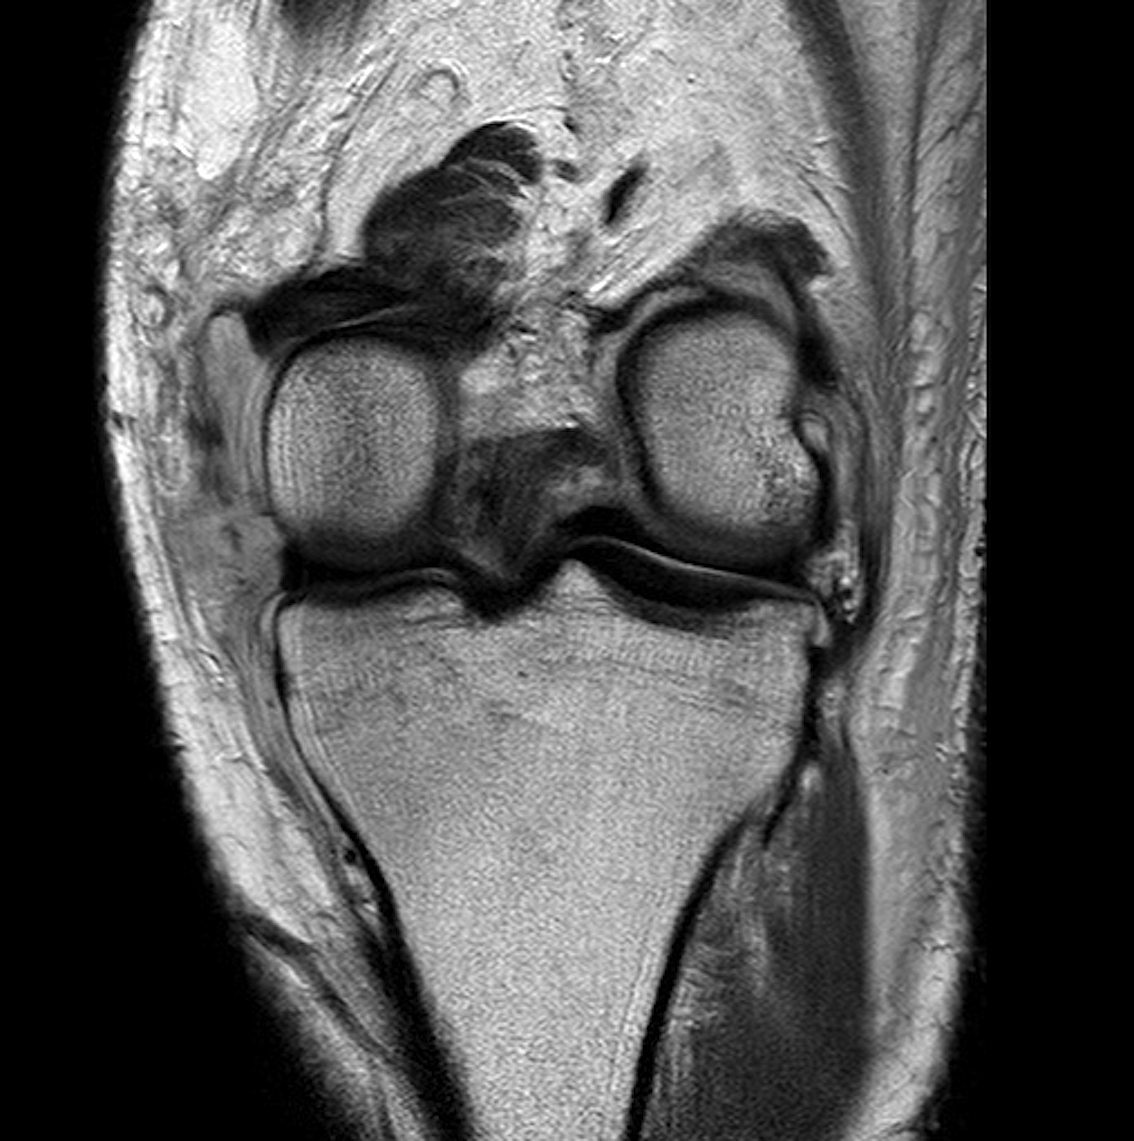

Medial dimpling Entrapped vastus medialis post knee dislocation on Coronal and Sagittal MRI

Coronal MRI of left knee demonstrating proximal MCL tear, with sagittal demonstrating complete disruption of ACL / PCL